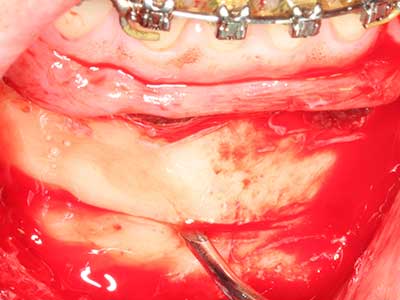

Indication: Bone splitting

Bone tissue is not simply a mineral structure but also contains a substantial proportion of collagen fibres. This means it not only has good compressive strength but also a degree of flexibility, which can be taken advantage of when performing bone augmentations. In the classical expansion procedure using bone splitting, the atrophied alveolar ridge is split longitudinally and carefully expanded after reaching an adequate osteotomy depth (Fig. 13-16), ideally without substantial removal of the periosteum (Brugnami, Caiazzo et al. 2014, Stricker, Fleiner et al. 2014). Screw and plate systems with increasing expansion distance have proven effective in separating the two bone lamellae while remaining below the fracture threshold. In general, residual bone widths of at least 3–4 mm are required (Chiapasco, Zaniboni et al. 2006) to guarantee adequate flexibility and sufficient bone coverage of the future implants. If necessary, a vertical relief osteotomy on one or both sides can improve flexibility. A combination with additional augmentation techniques, particularly on the buccal side, has been described as an alternative to the classical technique.

The splitting procedure is particularly atraumatic and there is no significant loss of dimension when using piezosaws, and there are no significant differences between implants in split jaws and implants in an alveolar ridge without a bone deficit (Chiapasco, Zaniboni et al. 2006, Danza, Guidi et al. 2009). However, sufficient continuous irrigation is essential, particularly with locally restricted and deep splitting to prevent thermal stress in the apical osteotomy regions.